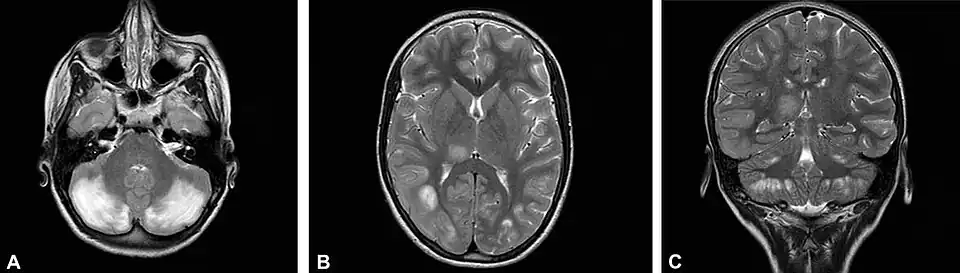

Наиболее ярко ЦФН проявляется при мутациях гена FOLR1, отвечающего за доставку фолатов в центральную нервную систему[4][5]. Ребёнок с мутацией рождается здоровым. Заболевание дебютирует чуть позже - в раннем детском возрасте - такими симптомами, как задержка психомоторного развития, атаксия, тремор, хорея, миоклонические приступы. На МРТ-снимках может наблюдаться гипомиелинизация. При немедленном назначении фолиновой кислоты можно добиться значительного улучшения состояния.

Иллюстрации

До и после возобновления терапии лейковорином при недостаточности ДГПР